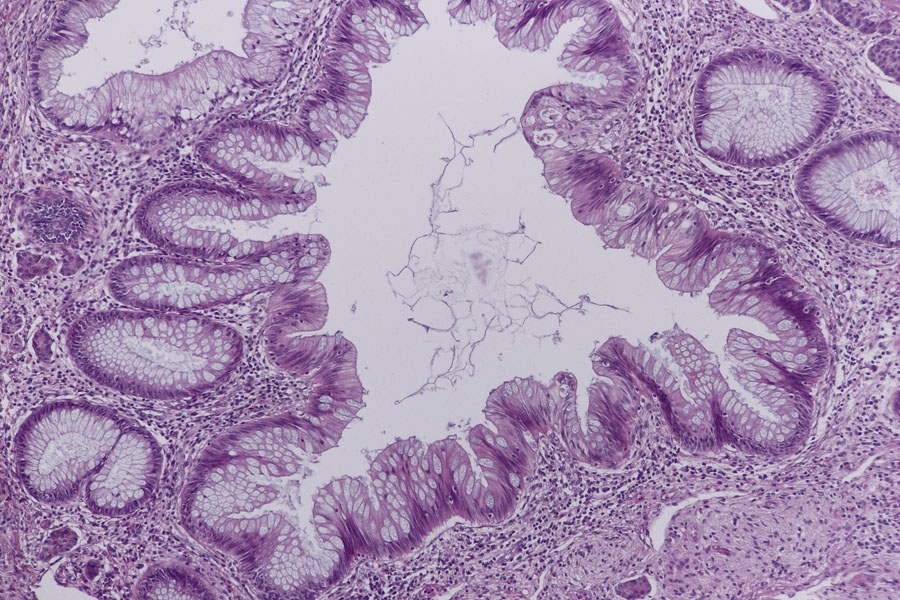

Im erste Blöckchen fand ich vom Aufbau einen typischen Appendix mit Mucosakrypten,

einer Submucosa mit Lymphfollikeln, einer inneren Ring- und einer äußeren Längsmuskelschicht so wie einem Mesenterialansatz. Was mich zuerst etwas irritiert hat war, das sich doch hier weniger Sekundärfollikel finden als ich es von anderen Präparaten gewohnt war. Das mag daran liegen, dass die meisten Appendixpräparate ja eine Appendizitis (Blinddarmentzündung) zeigen. Ronald Schulte hat das in einen tollen Beitrag im letzten Dezember beschrieben.

Ein zweites Präparat zeigt auch wieder den typischen Aufbau des Appendix und wenig gut abgrenzbare Sekundärfollikel.

Anfänglich war ich etwas irritiert durch zottenartige Bildungen der Schleimhaut, so wie eine sehr breite Submucosa. Doch sollten Zotten ja Blut-

und Lymphgefäße, so wie glatte Muskulatur enthalten die ich hier nicht gefunden habe, also sind es keine Zotten sondern nur Ausstülpungen

der Schleimhaut.